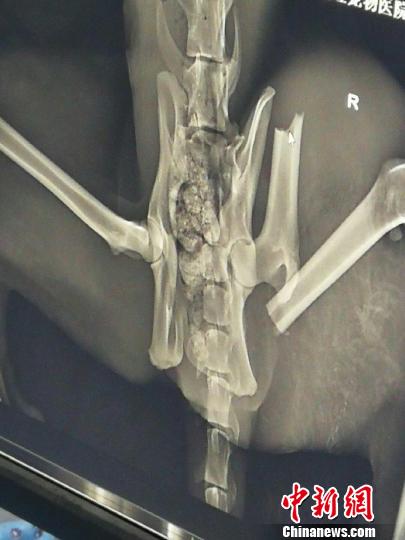

图为受伤雪豹X光片图显示,左后肢股骨骨折,髋骨左侧粉碎性骨折。青海省野生动物救护繁育中心供图

青海野生动物救护繁育中心负责人齐新章介绍,27日进行的拍片及验伤检查,否定了雪豹因被其它动物撕咬而受伤的推断,雪豹左后肢股骨骨折,髋骨左侧粉碎性骨折,判断为车辆撞伤;左后肢小腿皮肤与肌肉脱离,化脓严重,有腥臭味,判断为车辆撞击时与地面摩擦导致损伤;下嘴唇撕裂,上嘴唇刺穿,判断为车辆撞击时与地面摩擦导致损伤。